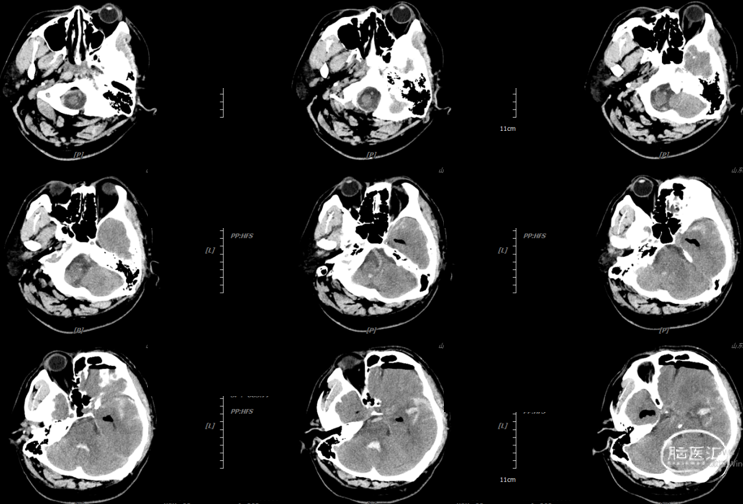

CTA:

辅助检查:头胸部CT平扫2026-03-14我院脑出血并破入脑室,请结合临床复查,蛛网膜下腔出血。双肺少许纤维灶,双肺坠积性改变,请结合临床隔期复查,双肺少许小结节,考虑低危结节可能,建议结合临床年度随诊复查双肺部分小叶间隔增厚,肺水肿不除外,建议结合临床短期复查,冠脉壁钙化灶,胆囊结石。头颈部CTA2026-03-14我院颅内动脉轻度粥样硬化性改变,左侧优势型椎动脉,椎基底动脉迂曲延长。